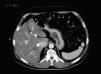

El 81,61% (n=253) de las TC realizadas mostraron resultado negativo. El 18,06% de las TC realizadas (n=56) identificaron un total de 72 incidentalomas. En una TC realizada a un paciente (0,32% de las TC realizados) con MC estadio T3a se identificó una imagen sugestiva de metástasis hepática única confirmada posteriormente mediante exéresis quirúrgica (fig. 2). Los incidentalomas más frecuentemente detectados fueron las lesiones ocupantes de espacio (LOE) hepáticas (26,39%, n=19), seguidas del nódulo pulmonar solitario (NPS) (15,28%, n=11) (fig. 3). El 48,61% (n=35) de los incidentalomas fueron no relevantes, mientras que en el 51,39% de los incidentalomas se realizaron estudios posteriores (n=37) (fig. 4). En 2 pacientes (0,64% de las TC realizadas) los incidentalomas se correspondieron con un adenocarcinoma de estómago y un carcinoma de pulmón (fig. 5). El 0,97% (n=3) de los TC fueron relevantes desde el punto de vista oncológico (un paciente con metástasis de melanoma y 2 pacientes con segunda neoplasia primaria).

TC de estadificación inicial de un hombre con melanoma cutáneo primario localizado en la espalda con estadio tumoral T3a. La flecha blanca indica la presencia de una lesión ocupante de espacio hipodensa en el interior del parénquima hepático confirmada como metastásica después de la resección y estudio anatomopatológico.